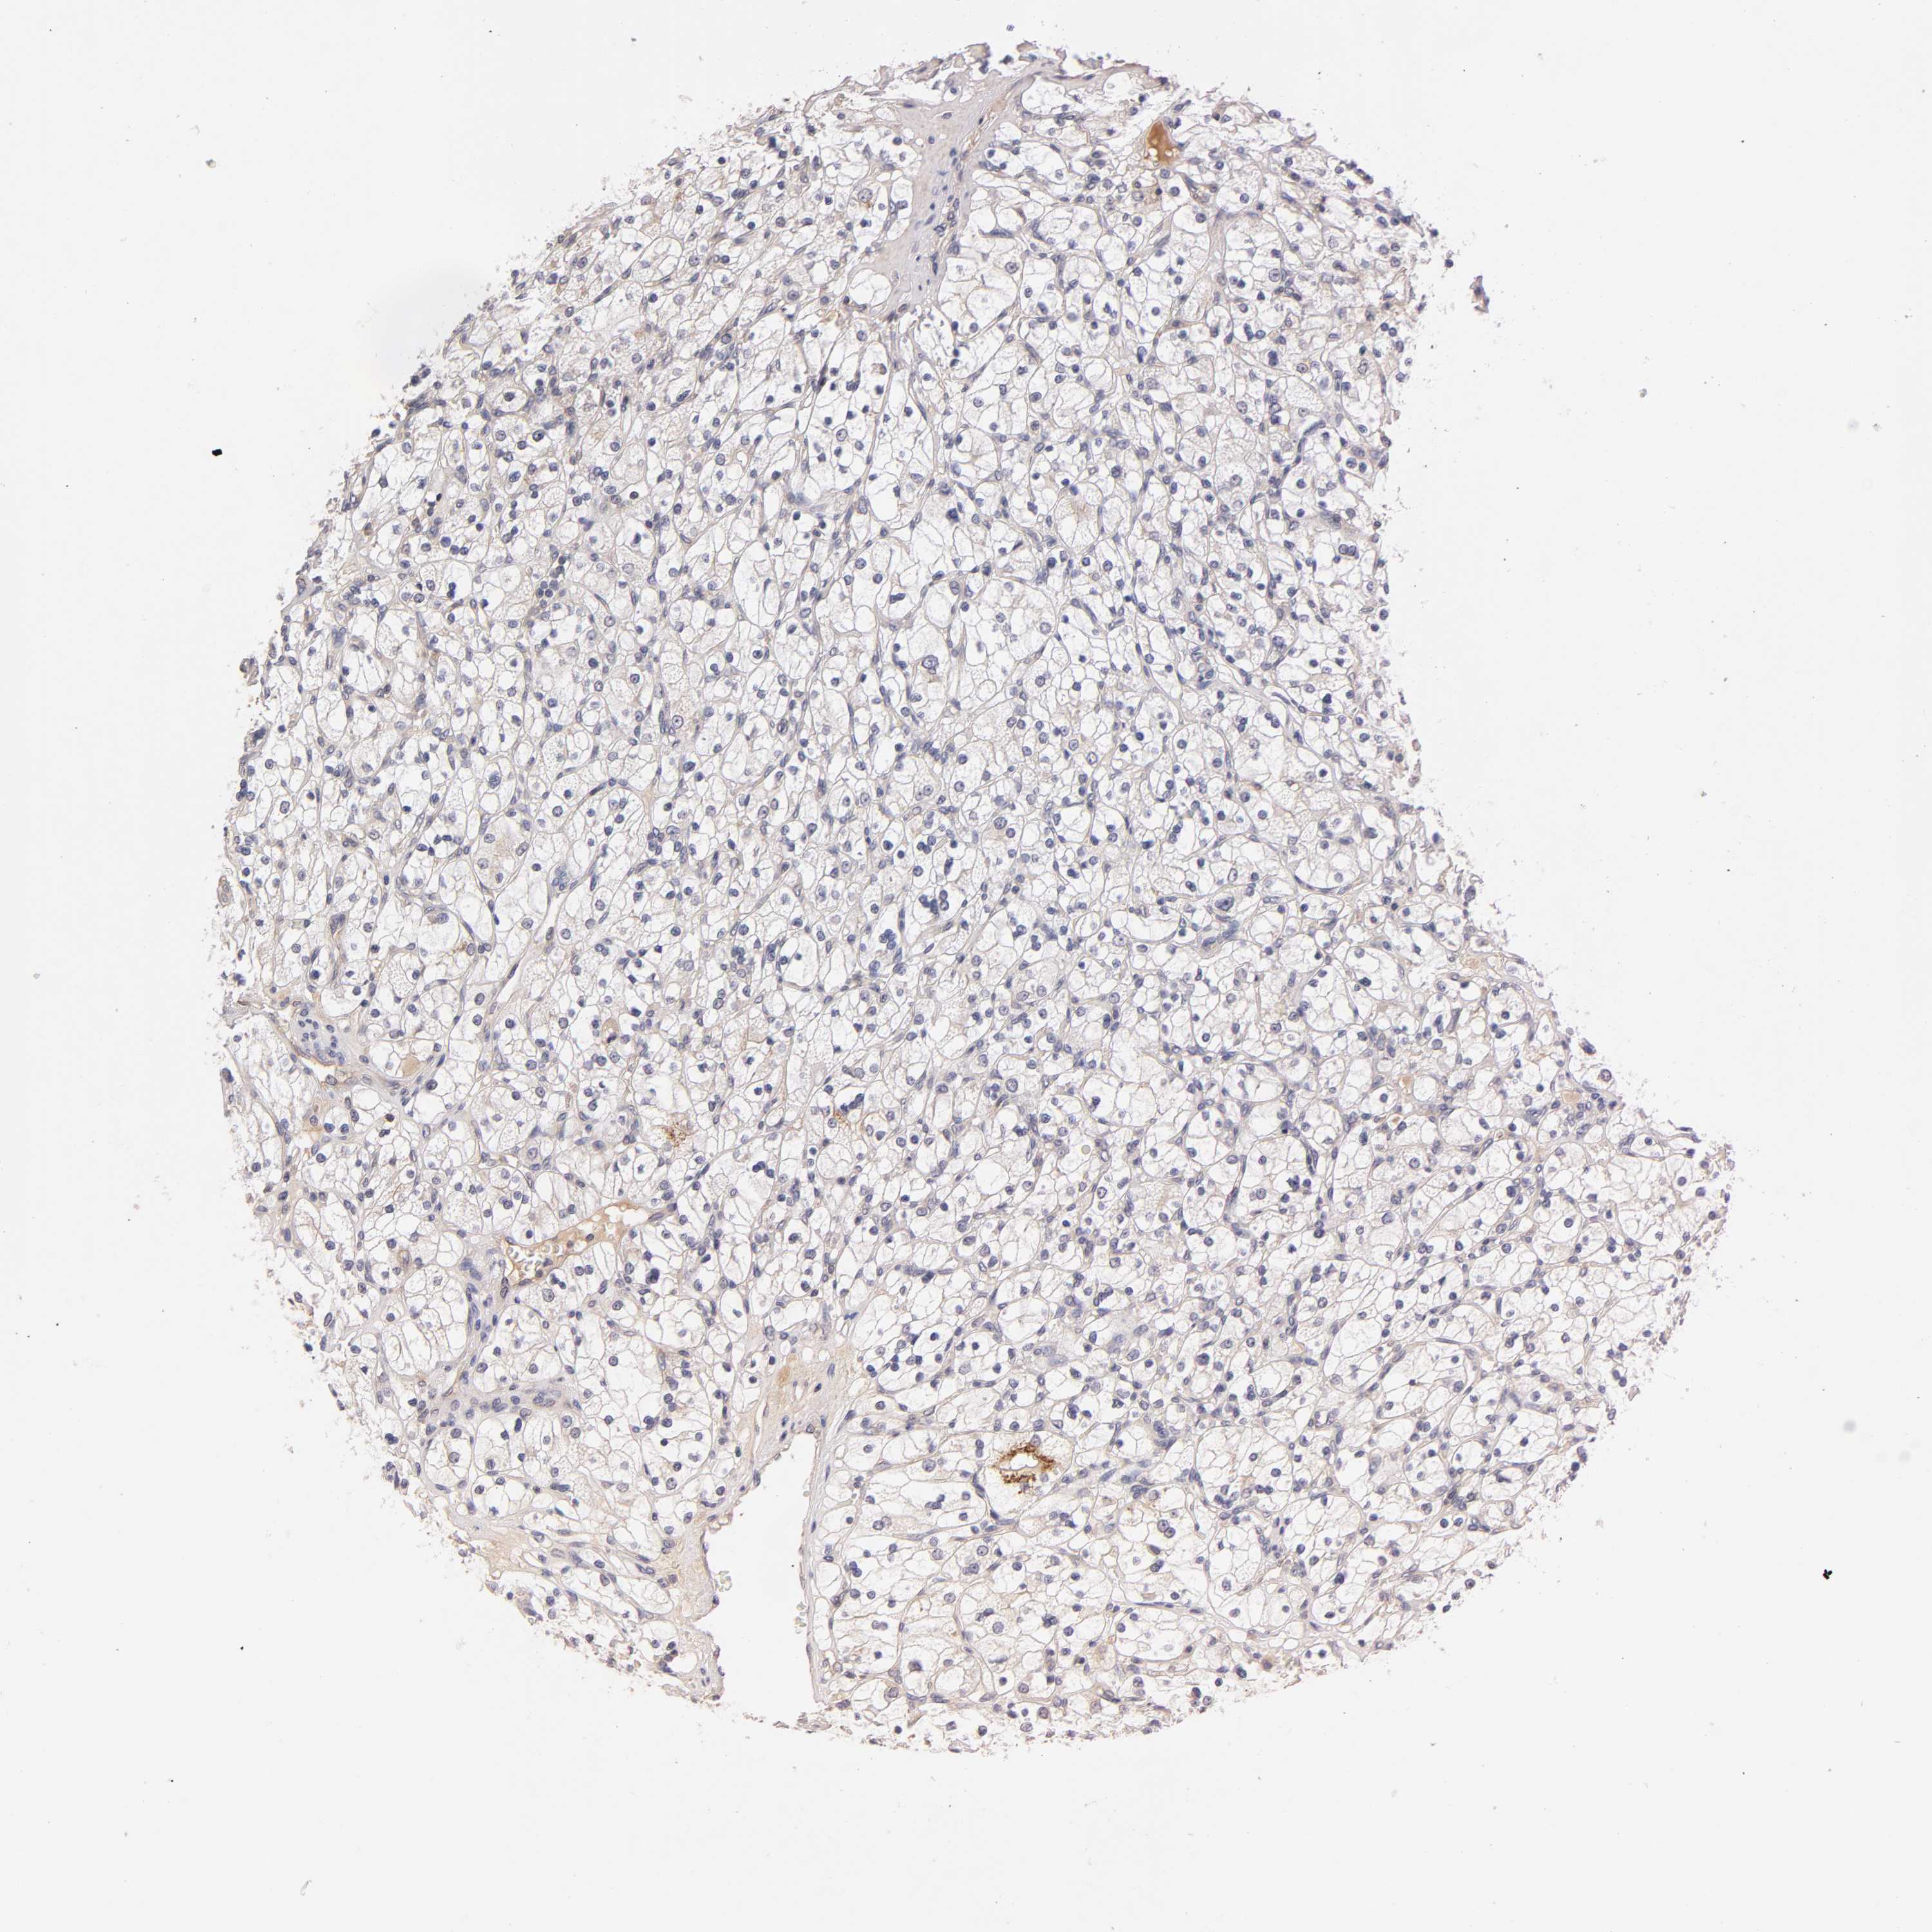

KIDNEY RENAL CLEAR CELL CARCINOMA (VALIDATION) - Interactive survival scatter ploti

RPS29 is not prognostic in Kidney Renal Clear Cell Carcinoma (validation)

: 2132.78

Average pTPM 2288.4

Number of samples 100